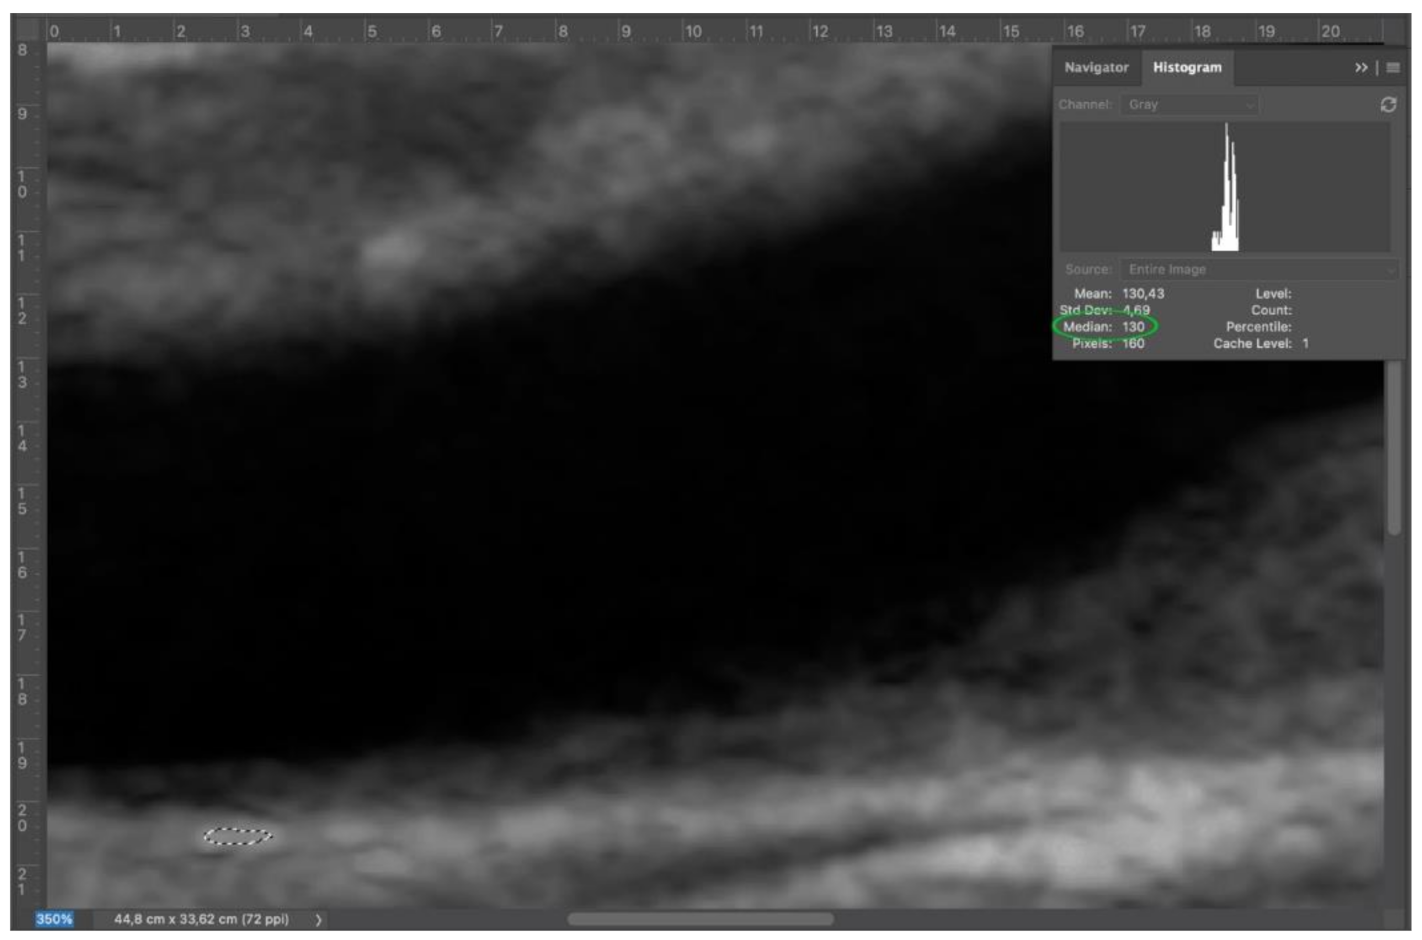

Second step: adventitia was set as a reference point. After zooming on adventitia around 300%, an area of adventitia (at least 100 pixel) was selected with lasso tool. The median value was obtained via histogram (Window > Histogram) (Figure 3).

Figure 3.

Step 2: select an adequate area of adventitia (dashed white circle), since it represents the key to perform a correct normalization.